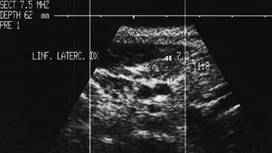

MetastaZE linfonodalE

Femeie de 65 ani. De 10 ani prima interventie de

tiroidectomie totala pentru neoplazie papilara infiltranta in tesutul muscular,

cu metastaze linfonodale. Terapie cu Iodi 131 in primii 5 ani.

Voluminoasa tumefactie laterocervicala dreapta (16 cc ) si paratraheala stanga

(3 cc), pozitiva la citoaspiratie pentru recidiva de neoplazie papilara.

Aceeasi de

65 ani. Nu se evidentiaza vascularizatie intratumorale

Aceeasi pacienta. IRM evidentiaza o formatiune neevidentiata ecografic, metastatica histologic.

Femeie de 29 ani. Linfonodul in regiunea

laterocervicala dreapta ( 7x12x23mm, 1 cc) in neoplazie papilara a tiroidei. Structura

parenchimatoasa, neomogenea, cu margini

nete, cu absenta hilului.Examen citologic: metastaza de neoplazie papilara.